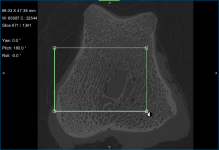

Screen capture of the completed tutorial